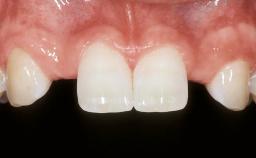

Replacement of Multiple Teeth in a Partially Dentate Posterior Mandible with a Fixed Dental Prosthesis Using a Flapless Approach

Her chief complaint was her inability to masticate efficiently due to the recent loss of her mandibular second premolars and first molars bilaterally. She expressed a desire for fixed prostheses in the shortest possible time due to her advanced age, requesting that replacement teeth should look as natural as possible. She was otherwise comfortable and not experiencing any symptoms from her teeth.

Prosthesis Type FDP